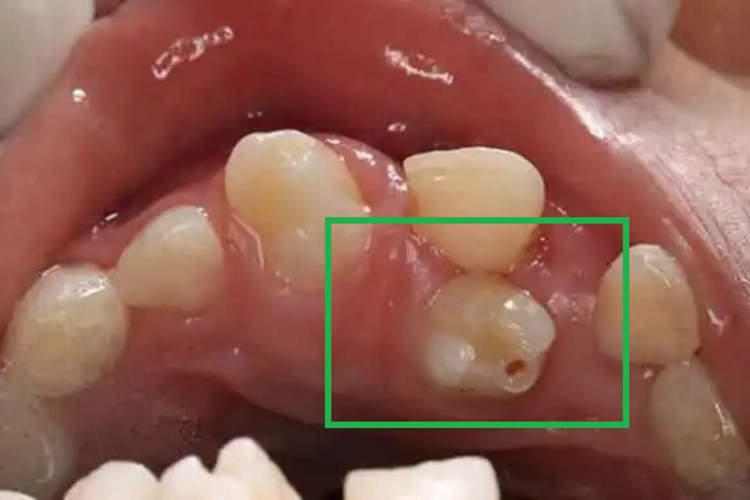

多生牙患者局部可有单个或多个多生的牙齿,导致牙齿排列拥挤、牙间隙大、牙移位,同时部分牙齿的表面可有大小不一的小孔,为圆形、类圆形。